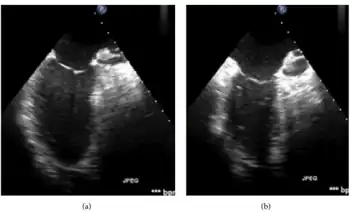

Imaging techniques such as echocardiography, ventriculography, and nuclear imaging can be used to detect a contractile dysfunction following reperfusion after an episode of ischemia.[1] The area of dysfunction should also maintain normal perfusion, detected via Positron Emission Tomography, echocardiography with contrast, and/or thallium scintigraphy in order for a diagnosis of myocardial stunning to be considered.[1] However, there are many practical challenges to diagnosing myocardial stunning using these methods. Accurate detection of regional myocardial blood flow and contraction function abnormalities must be detected at levels of high sensitivity.[2] The diagnosis of myocardial stunning must also be differentiated from other conditions such as hibernating myocardium and persistent (silent) subendocardial ischemia, which can also co-exist with superimposed stunning.[2]